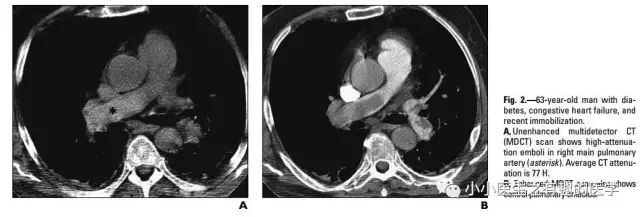

文献五

国外有高手专门研究了CT平扫诊断肺栓塞的可靠程度。

高分辨CT平扫管腔内高密度征象诊断肺栓塞的敏感性36.0%, 特异性99.0%,阳性预测值90.0%,阴性预测值85.6% 。

高分辨CT平扫管腔内高密度征象诊断中心肺栓塞敏感性66.7%, 特异性99.1%。

5.Tatco V R, Piedad H H. The validity of hyperdense lumen sign in non-contrast chest CT scans in the detection of pulmonary thromboembolism[J]. International Journal of Cardiovascular Imaging, 2011, 27(3):433-440.